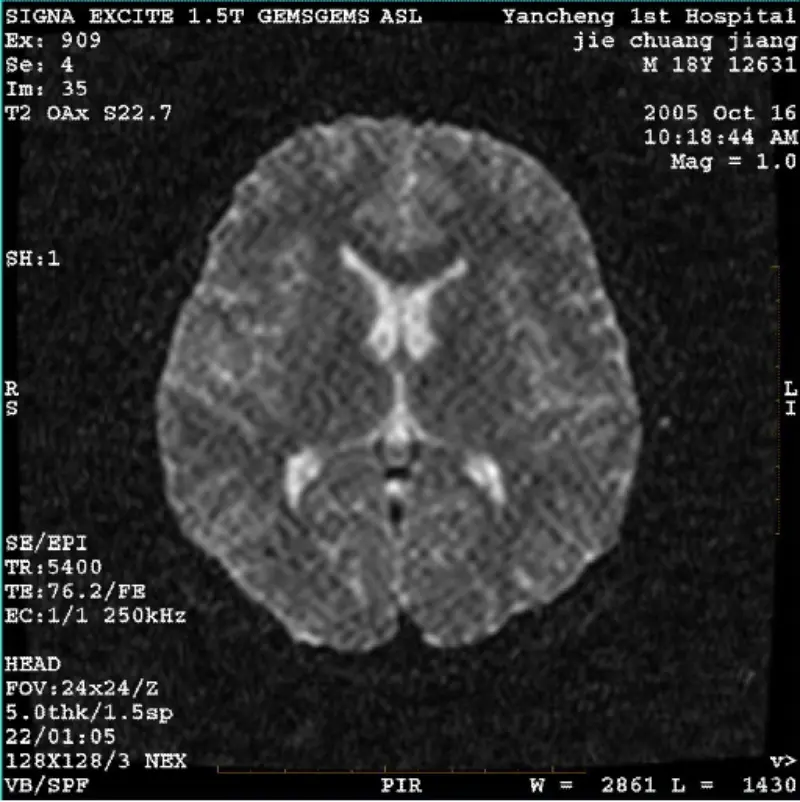

مزید پڑھسسٹم: 1.5T Signa Twin Excite II (سافٹ ویئر ورژن 11.0M4) مسئلہ/علامت ڈی ڈبلیو آئی (زوم موڈ اور پورے موڈ) اور فیسٹا (زوم موڈ اور پورے موڈ) والی تصویر ظاہری جالیدار یا کورڈورائے آرٹفیکٹ چاہے باڈی کوائل یا ہیڈ استعمال کرتے وقت کنڈلی، دیگر معمول کی تصویر عام لگتی ہے